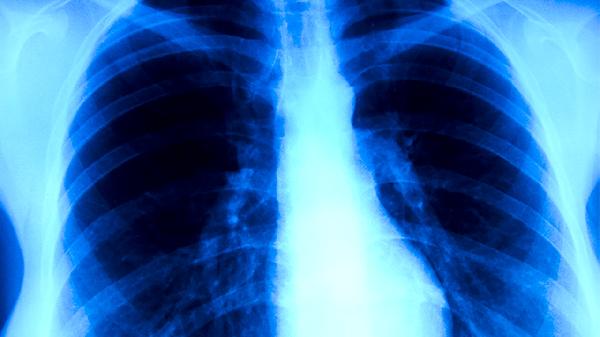

肺結核康復期患者需保持規(guī)律三餐,烹飪方式以蒸煮燉為主。每周進行3-5次有氧運動如快走、太極拳等,運動強度以微微出汗為宜。定期復查胸部影像學,出現持續(xù)兩周以上的午后低熱、夜間盜汗等癥狀應及時就診。居家環(huán)境保持通風干燥,每日開窗換氣2-3次,每次不少于30分鐘。